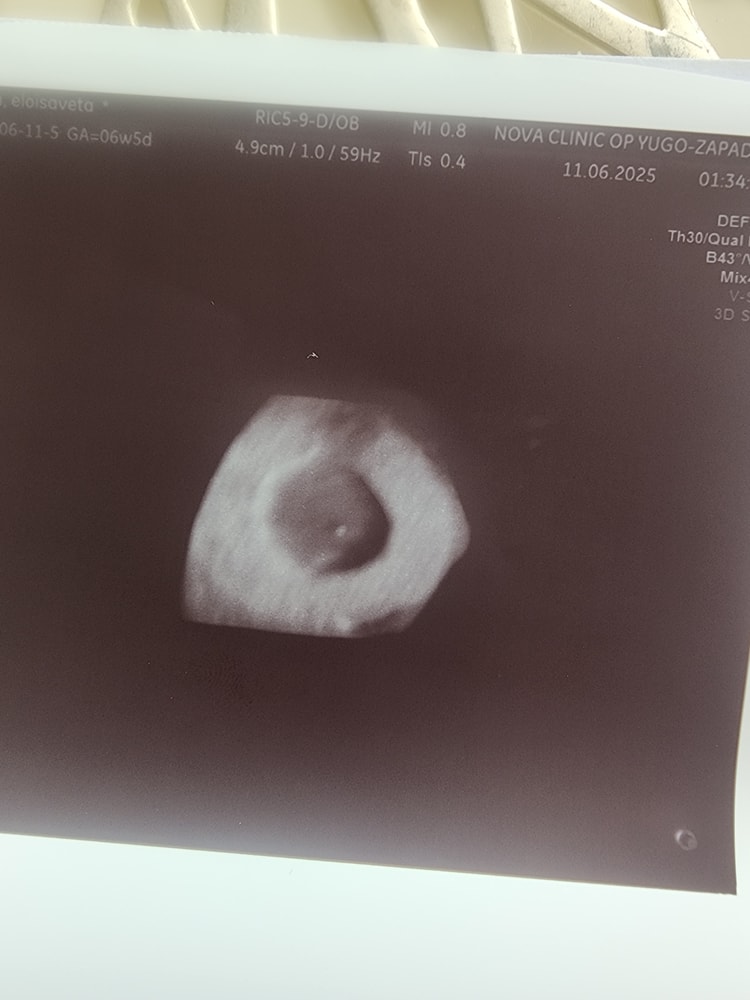

УЗИ 6 недель 5 дней

Результаты УЗИФиг знает какой дпп

На УЗИ даже не смогли найти эмбрион, повели на более мощный аппарат и там вот такая маленькая точечка

Я так понимаю,что по сроку отстаёт. Видимо придётся делать вакуум или МА